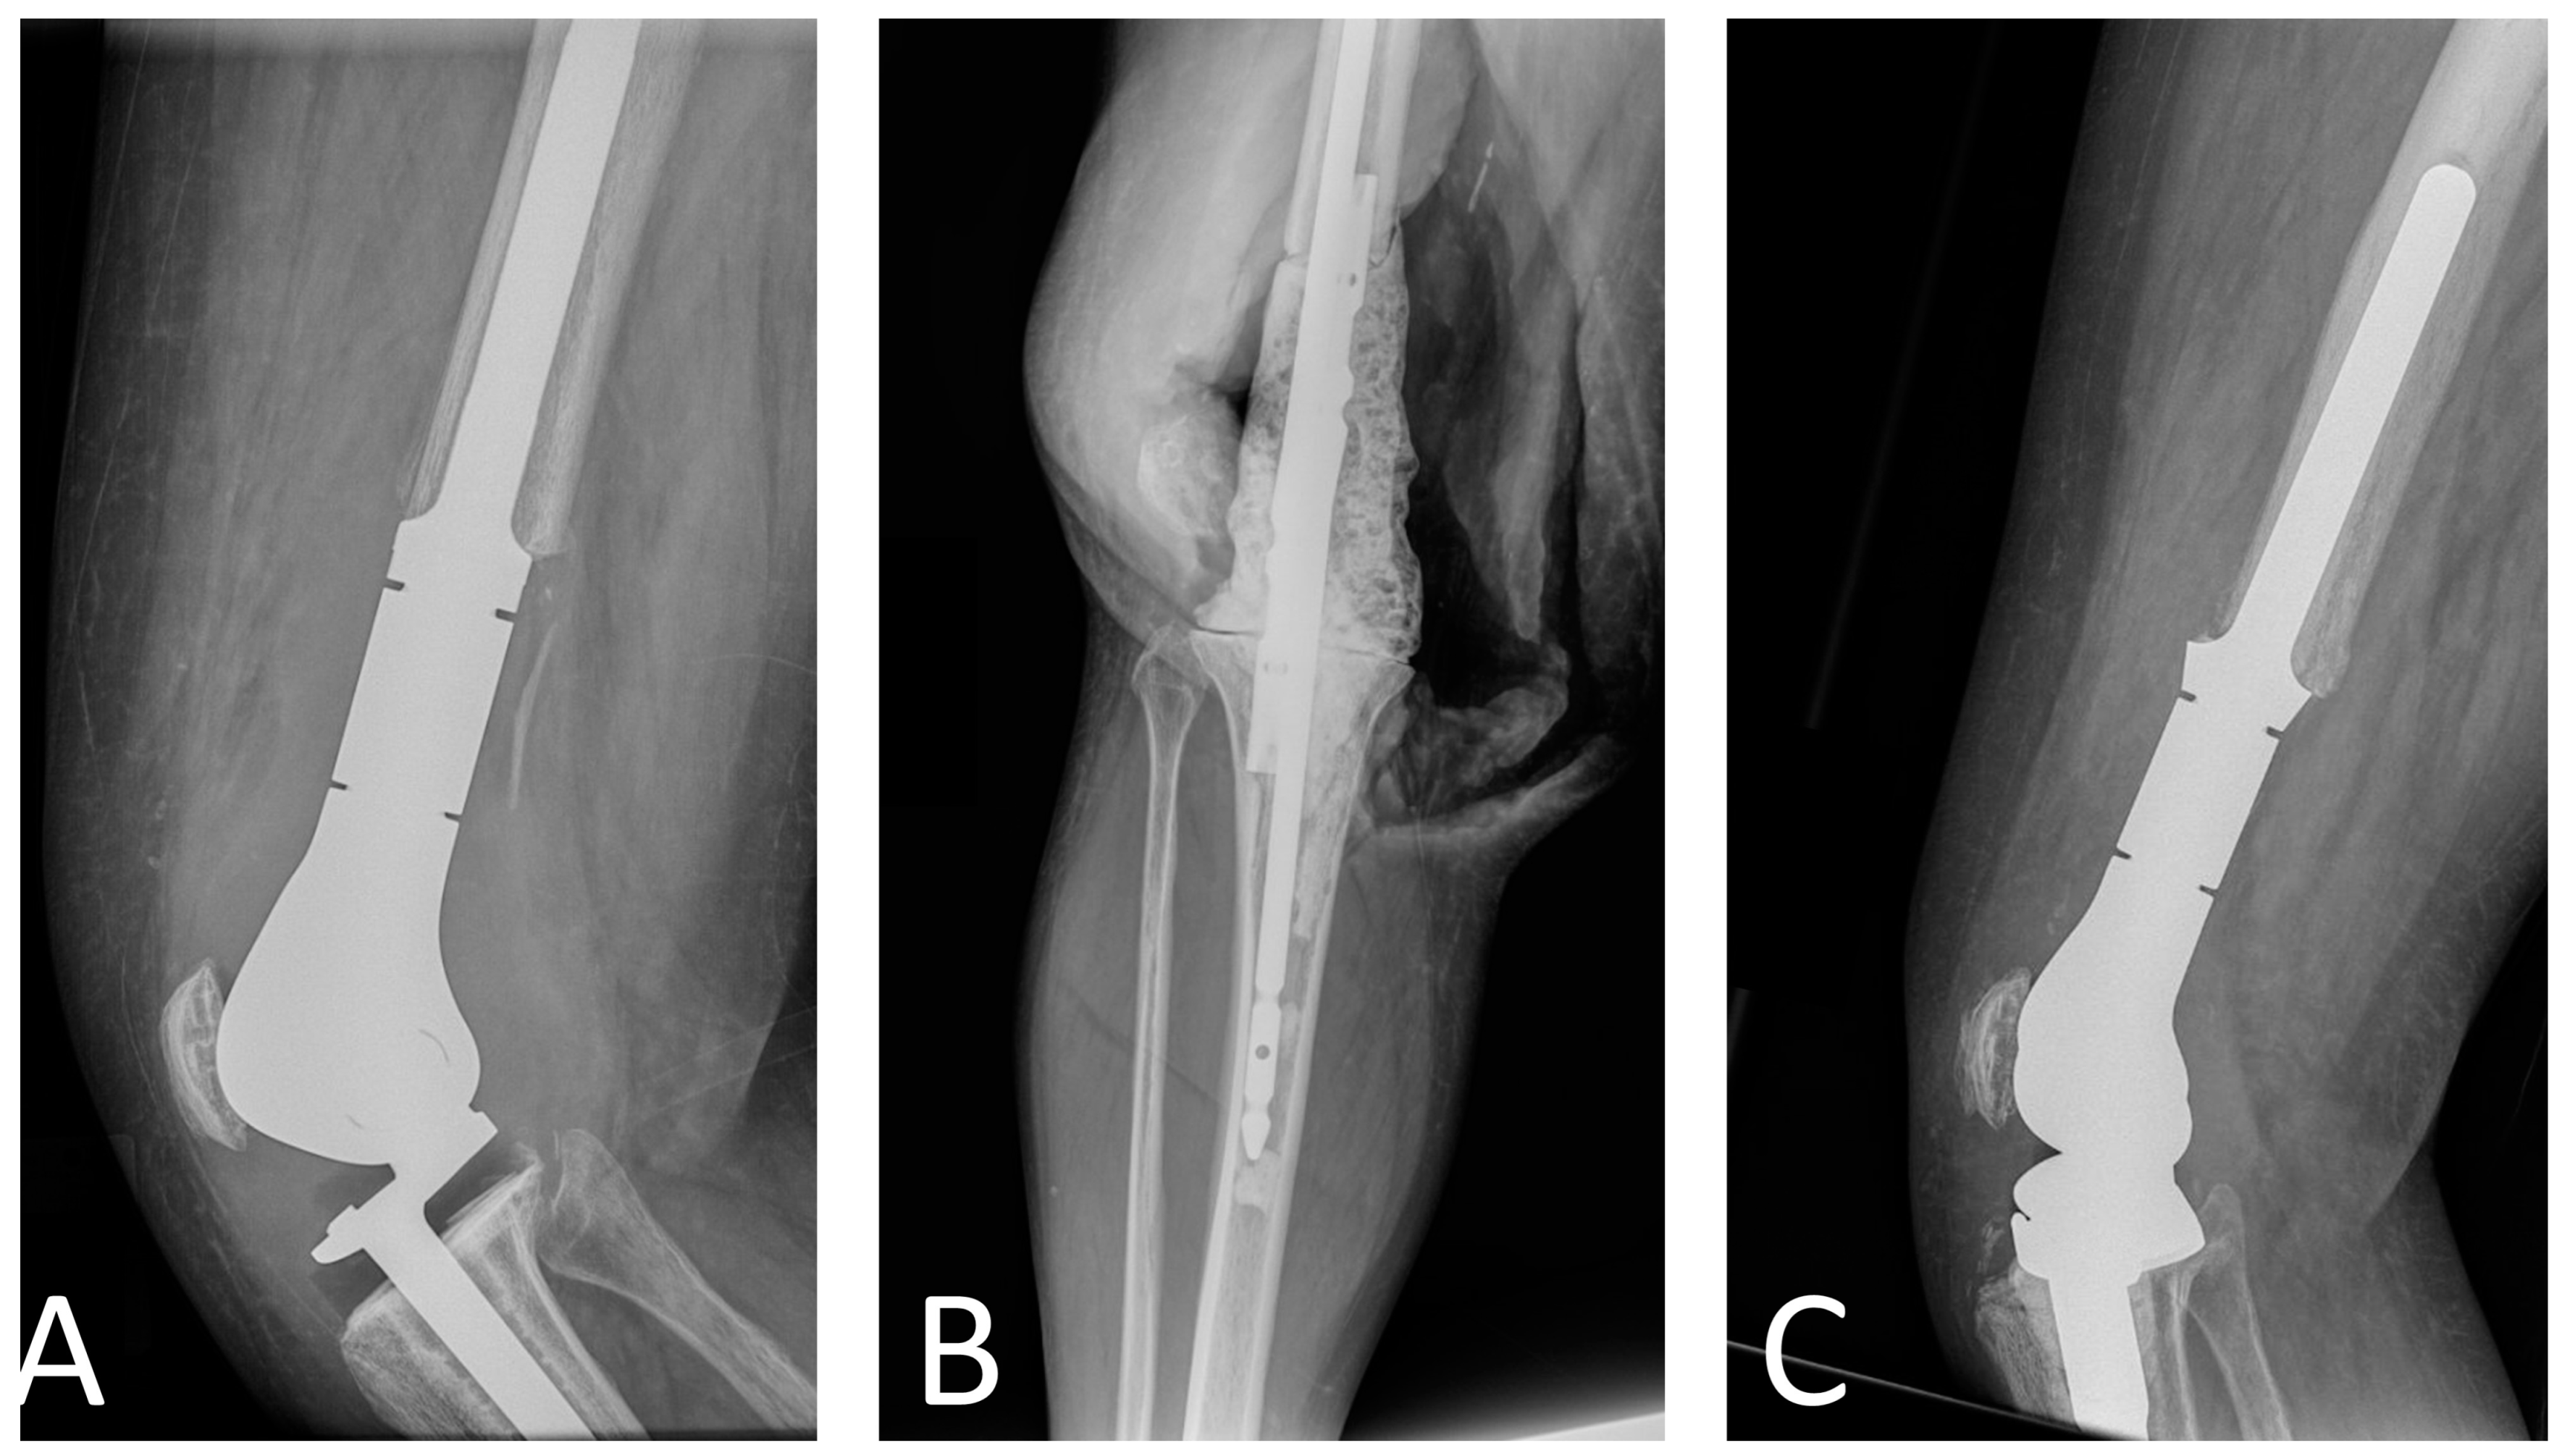

- Pala, E.; Trovarelli, G.; Angelini, A.; Maraldi, M.; Berizzi, A.; Ruggieri, P. Megaprosthesis of the knee in tumor and revision surgery. Acta Biomed. 2017, 88, 129–138. [Google Scholar] [CrossRef]